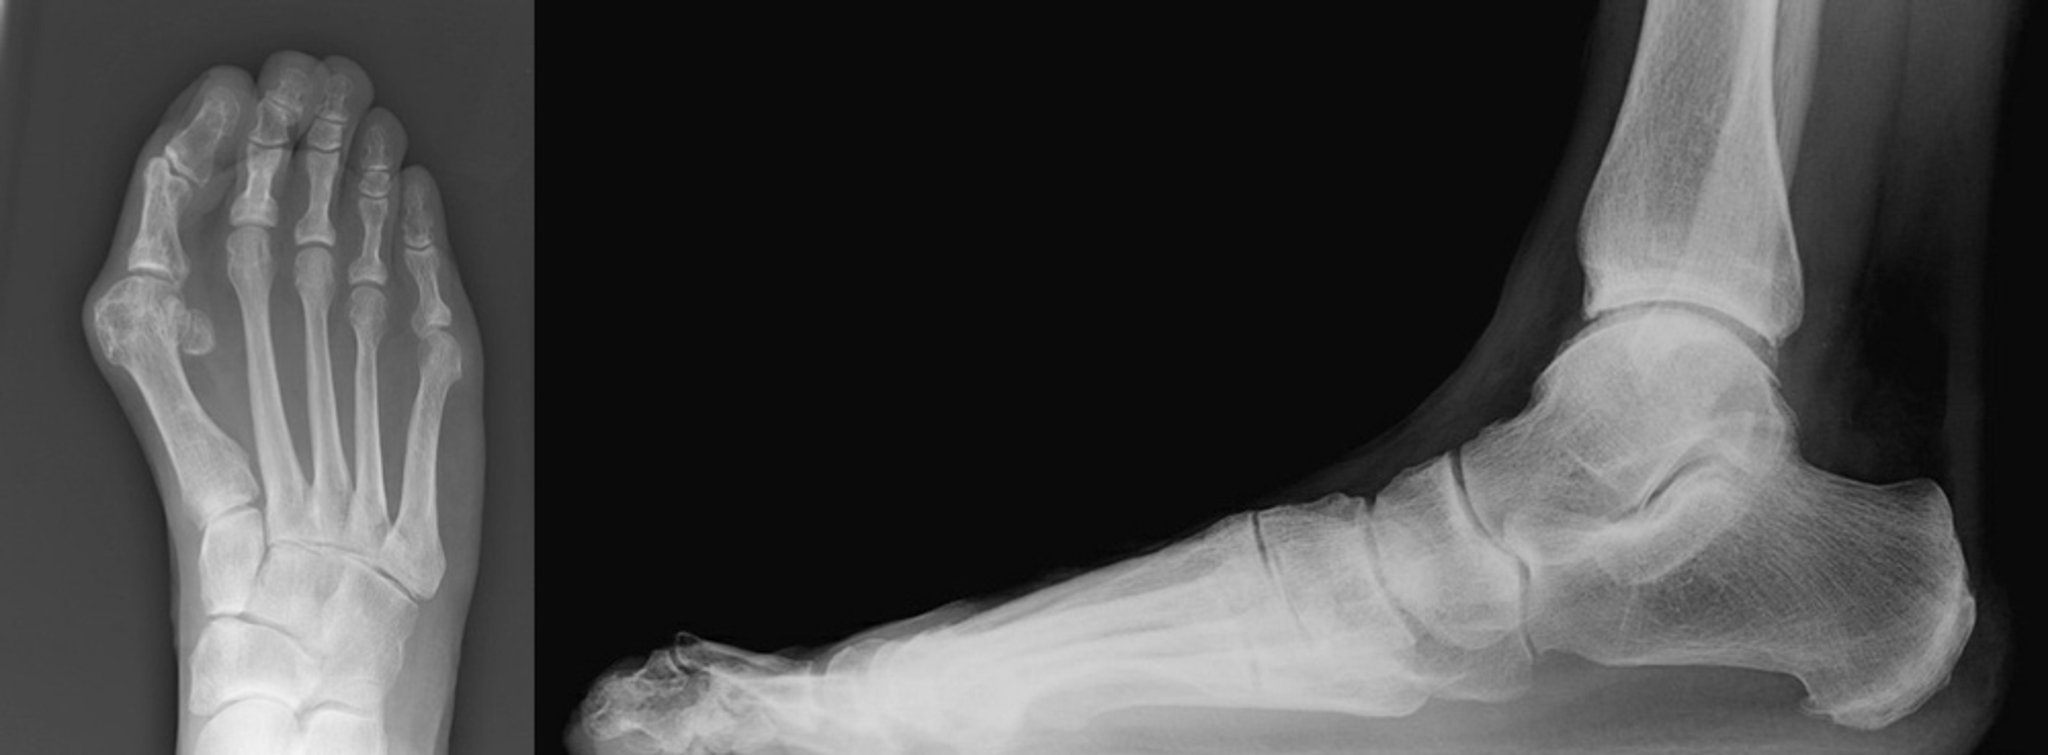

Рентгенограми буніона з молоткоподібним пальцем стопи

Anteroposterior and lateral views of a bunion with a hammertoe of the second toe are shown.

The anteroposterior view shows severe hallux valgus with medial deviation of the first metatarsal bone. There is abutment of the hallux to the second toe. The second digit is deviated laterally with narrowing of the second metatarsophalangeal joint (left).

The lateral view shows the second toe is dislocated at the metatarsophalangeal joint. There is hyperflexion at the proximal interphalangeal joint with hyperextension of the distal interphalangeal joint of the second toe (right).

Images courtesy of James C. Connors, DPM.